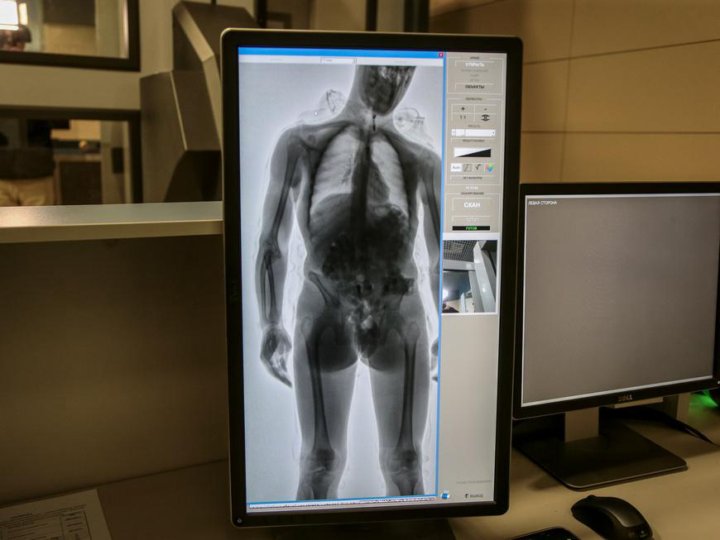

Рентгеновские снимки плат в высоком разрешении